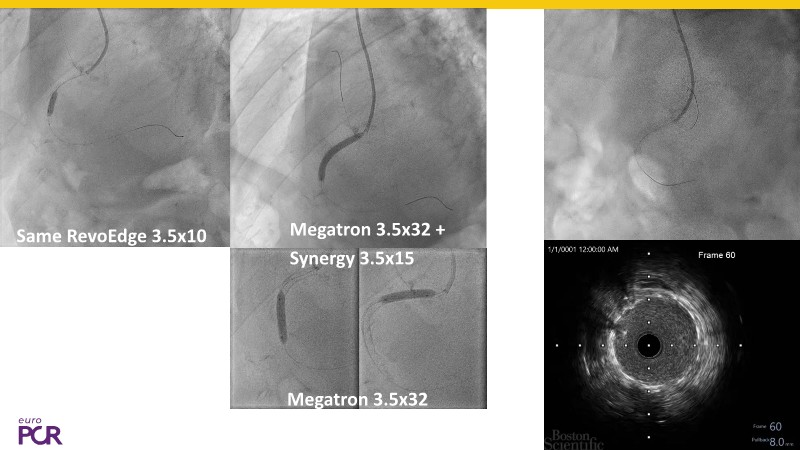

Discover how the next-generation RevoEdge high-pressure cutting balloon is transforming PCI with innovative design and proven clinical outcomes. This session presents a multicenter randomised trial and real-world case discussions, showcasing RevoEdge’s effectiveness in tackling resistant, complex lesions—including long, tortuous, and fibrotic cases. Learn practical tips, tricks, and intravascular imaging insights to optimize lesion preparation and improve patient outcomes. Don’t miss this opportunity to see how RevoEdge helps you cut through challenges and conquer PCI complexities.

- To explore the innovative design of RevoEdge: the next-generation high pressure cutting balloon

- To learn about the clinical benefits and tips and tricks of using RevoEdge high pressure cutting balloon in different types of complex lesions through case-based discussion